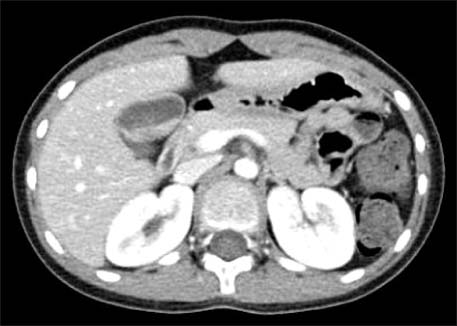

Fig. 3

Ultrasonography after 6 weeks of conservative treatment shows the disappearance of previous gallbladder stones (case 2).